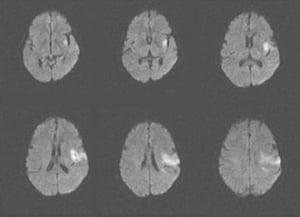

Гострий ішемічний інсульт (МРТ)

This MRI scan shows an area of restricted diffusion consistent with an acute ischemic stroke in the left insular and frontal lobes.

Image courtesy of Ji Y. Chong, MD.